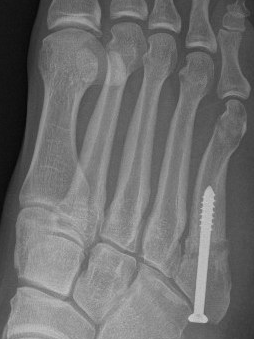

Screw fixation Zone 2 nonunion

Screw fixation Zone 3 nonunion

Entry point

- 5th metatarsal is not straight

- high and medial to get straight shot

- avoids plantar insertion peroneus brevis

- screw diameter 3.5 / 4.5 / 5.5 / 6.5

- screw threads must be distal to fracture site to allow compression